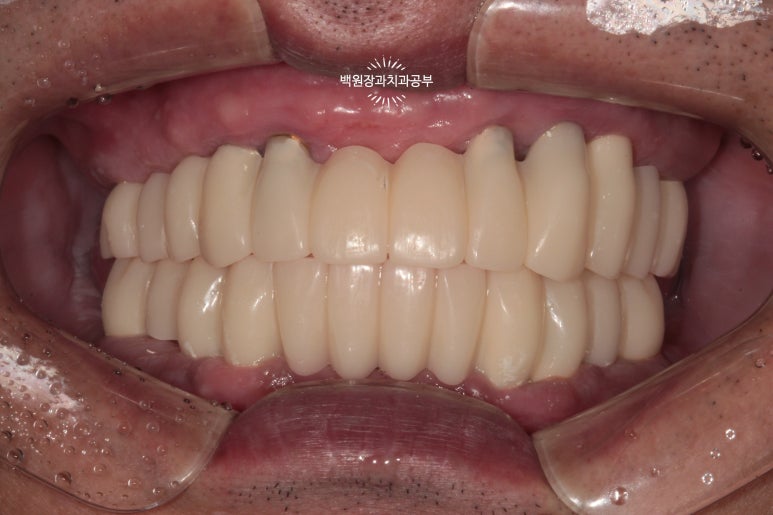

최종 보철물.. 드디어 제작이 되었습니다.

사실 정말 정말 감동적인 순간입니다... 우리 환자분께서 이 날만을 얼마나 기다리셨을까요.....

전체 임플란트를 완성하는데 전체 치료기간은 약 8개월 정도 걸렸습니다. 상당히 빨리 졸업하신 편이에요!

정면에서 보시면 임시 치아와 다르게 훨씬 깊이감 있는 색상으로 제작되어 자연스럽고, 완성도 있는 형태를 확인하실 수 있습니다.

그리고 치과용 파노라마로 확인해보시면, 정확한 위치에 정확한 보철물이 제작되어 상당히 조화로운 결과를 확인하실 수 있으실거에요! 치과의사로 살면서 가장 기쁘고 감동적인 순간 중 하나입니다.

정말 너무너무 보람찹니다 :) ㅎㅎ 환자분께서도 굉장히 만족해하셨어요!

금호동 전체 임플란트 전문 치과 대표 원장인 저와 보철과 원장님이 함께 최선을 다해 작업하였습니다.!!

이래서 치과 전문의가 중요합니다!!!

전체 임플란트는 절대 쉬운 치료가 아닙니다.